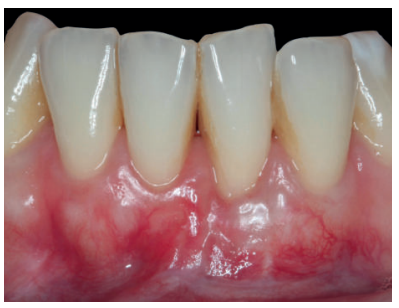

Se realizó control a la semana de la intervención (Figura 4) y tras 15 días se retiró la sutura, observando la revascularización del injerto y la epitelización del área cruenta apical al sobre (Figura 5). Se realizó seguimiento al mes (Figura 6), a los 3 meses (Figura 7) y al año y medio del procedimiento (Figura 8).